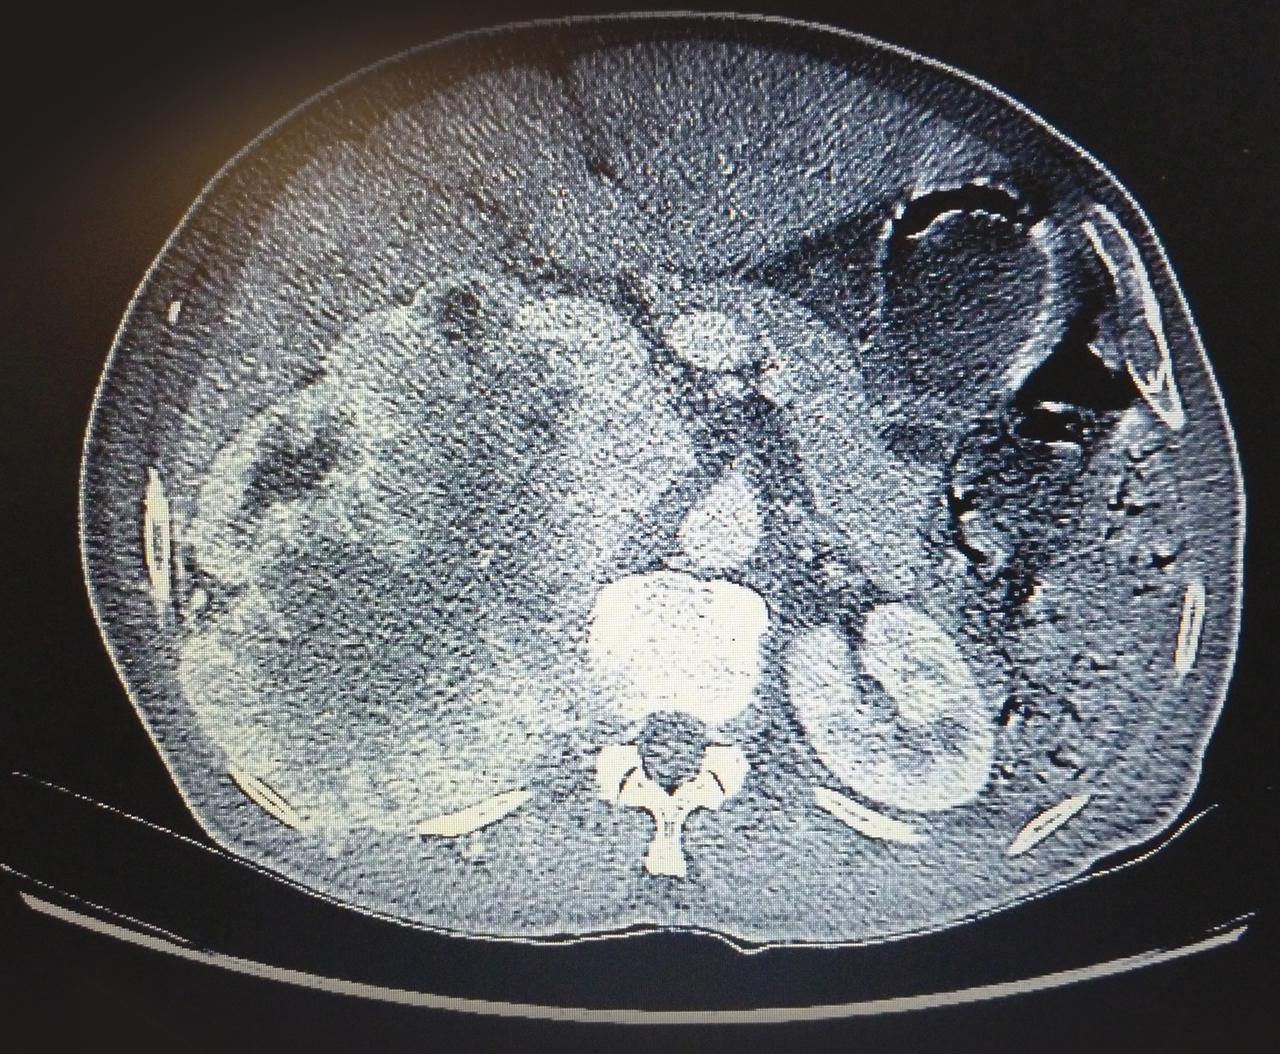

Quel est votre diagnostic ?

Il s'agit d'un cancer du rein.